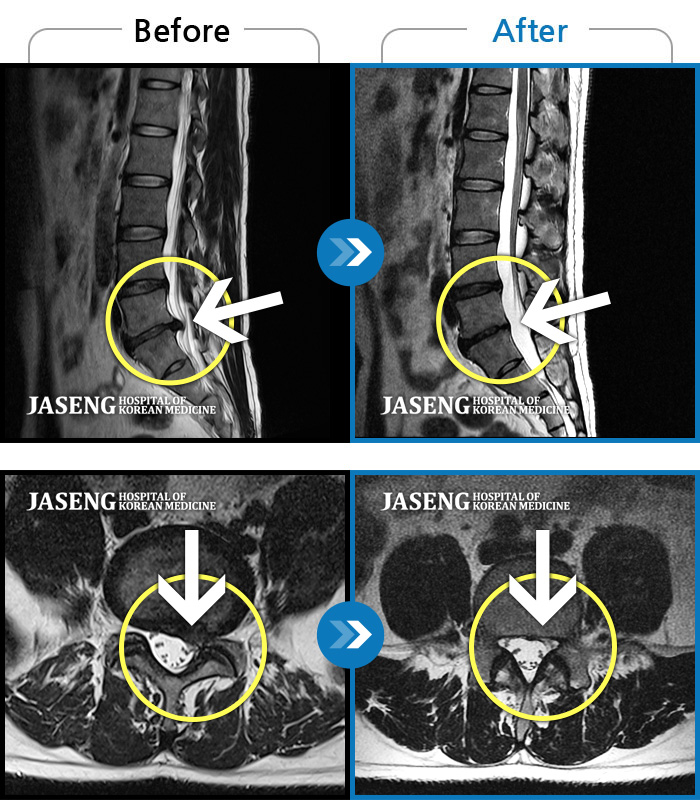

ȯںп Ǹ ǿ ԿǾ, ο ġ ۿ Ƿ ġḦ Ͻñ ٶϴ.